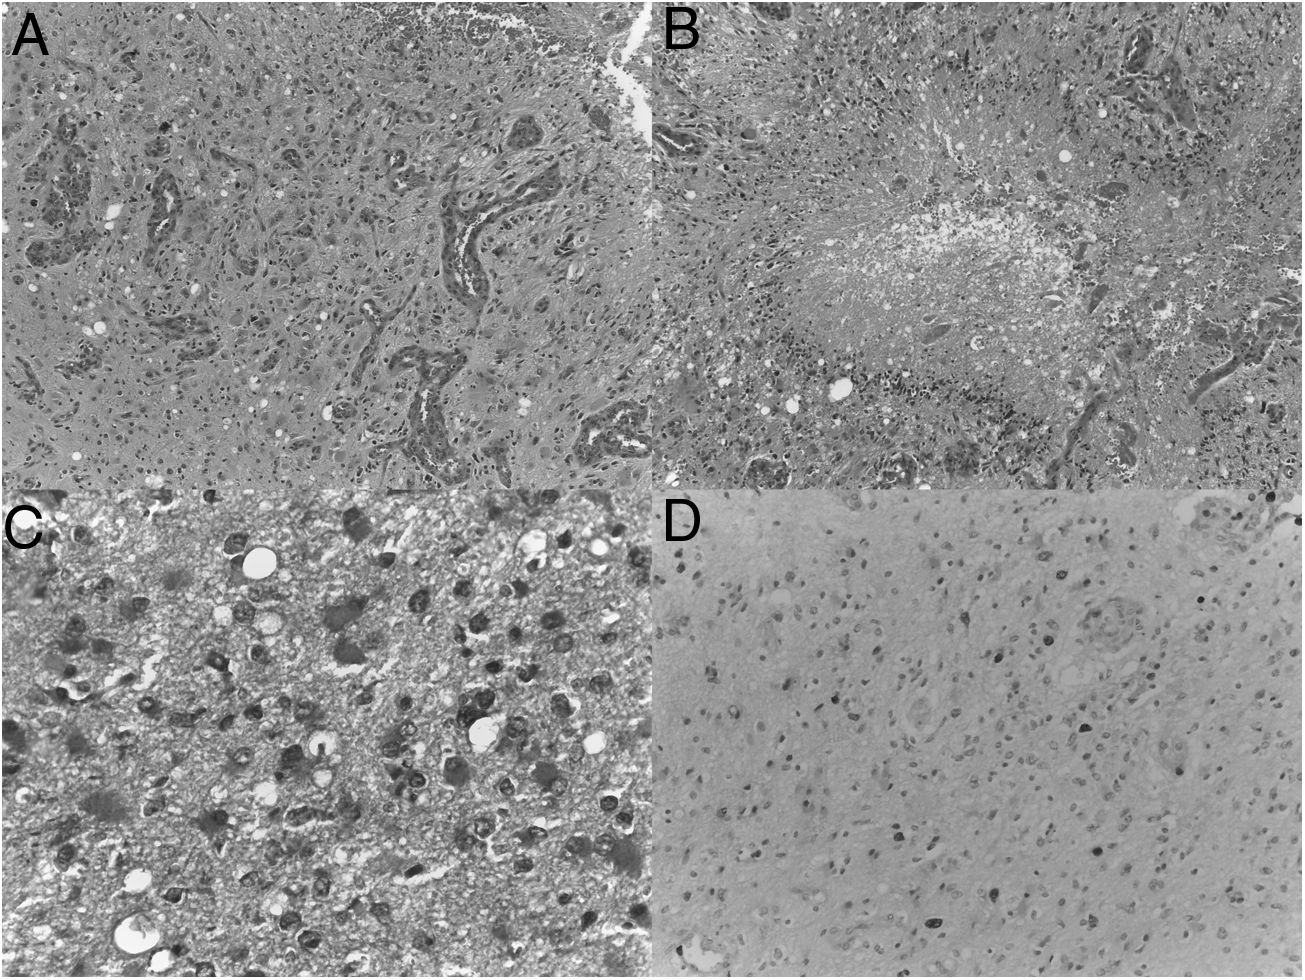

Material and methodWe realize a systematic analysis and identify important factors for long survivor patients. We also show an own case with more of 20 years of survival. We make a new pathological study of the old paraffin block of this patient.

ResultsThe most important variable associated with long-survival between all multivariant studies is the age. When we try to find genetic and molecular alterations in glioblastoma associated with prolongated survival, the MGMT promoter methylation play the most important role. We find a correct diagnosis in the current analysis of our patient’s sample with very long survival.

Material y métodosSe realiza un análisis sistemático de la literatura identificando los factores que pueden influir en los pacientes de larga supervivencia. Se identifica un caso en nuestro medio de más de 20 años de supervivencia realizándose un análisis actual del bloque de parafina que se conservaba del paciente.

ResultadosLa variable que más se asocia a la larga supervivencia en todos los análisis multivariantes es la edad, aunque, cuando se analiza las características genéticas y moleculares de los tumores, parecen existir otras variables como la metilación del promotor MGMT que juegan un papel muy importante. El análisis anatomo-patológico actual de la muestra comprueba la certeza del diagnóstico en nuestro paciente de muy larga supervivencia.